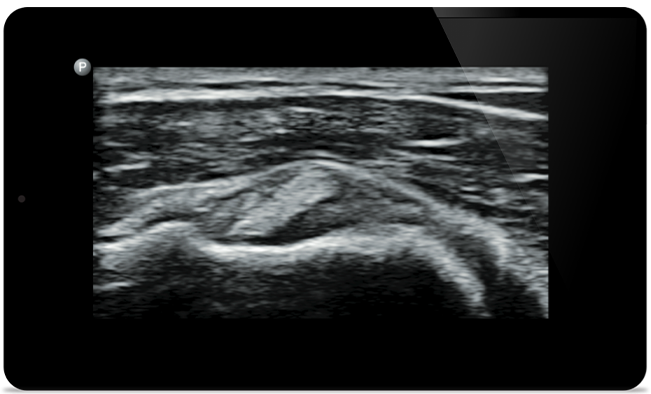

Lumify hilft Ihnen, die feinen Details in Muskeln, Gelenken, Bändern, Sehnen und Knorpeln zu erkennen, um Verletzungen präziser zu diagnostizieren.

Lumify unterstützt Sie bei der Beurteilung von Patienten von Kopf bis Fuß, sei es bei Plantarsehnenentzündung, Sehnenscheidenentzündung oder Schleimbeutelentzündung in der Patellasehne oder sogar bei Schulterinstabilität in der Rotatorenmanschette.

SonoCT verbessert die Gewebedarstellung und eliminiert Artefakte. So entstehen bei bis zu 94% der Patienten Bilder in besonders guter Qualität im Vergleich zu konventioneller Bildgebung.